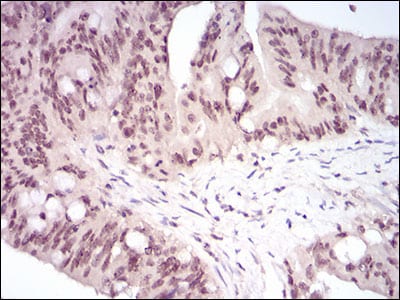

分类: 科研抗体货号: 30696别名: HSTF1应用: IHC,IF反应种属: Human